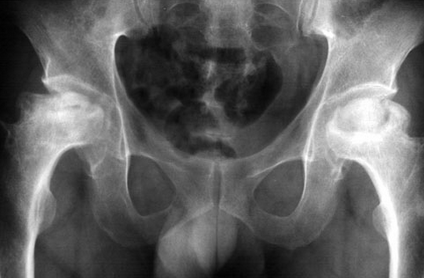

股骨頭壞死的治療,什么是股骨頭壞死

股骨頭壞死是由于不同病因破壞了股骨頭的血液供應,造成血供障礙,因為缺血導致骨組織營養中斷、骨細胞死亡,以不定區域的骨小梁和骨髓壞死為特征的骨科常見病。

股骨頭壞死分期及療效如下所示:

I期:無或隱痛 ;股骨頭外觀正常,軟骨、骨小梁結構稍模糊,或呈斑點狀骨質疏松,可見輕度密度增高區或減低區,甚至可以陰性。可以治愈

II期: 疼痛不適,活動勞累后加重,休息后減輕、可有跛行。骨質密度正常或有明顯斑點狀密度增高,頭無塌陷,有分界明顯的骨硬化區。可以治愈

III期:疼痛明顯、跛行;軟骨下骨折,出現"新月癥"或扇形骨折 ;可以治愈

IV期:跛行嚴重、出現功能障礙;全頭或大面積塌陷,股骨頭扁平,關節間隙變窄 ,可臨床治愈

V期 :功能明顯障礙;股骨頭變形、死骨碎裂、關節間隙明顯變窄??梢娖瑺蠲芏仍龈哂???删S護關節基本功能

VI期:功能嚴重障礙;股骨頭肥大、變形、脫位、關節間隙完全消失、髖臼不光滑甚至硬化增生;建議行關節置換術配合藥物治療。